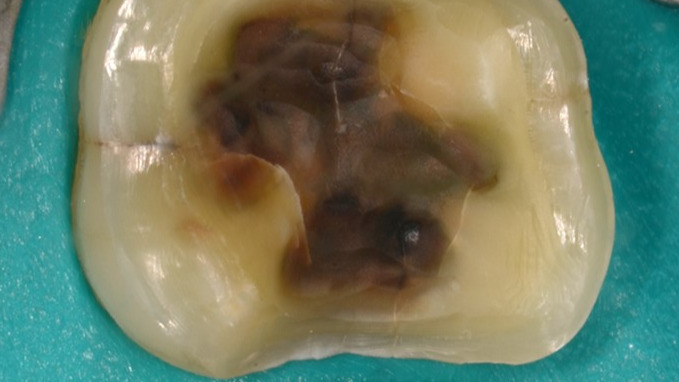

● Savoir diagnostiquer les fêlures dentaires

● Connaitre les différentes catégories de fêlures dentaires

• Moyens de diagnostics